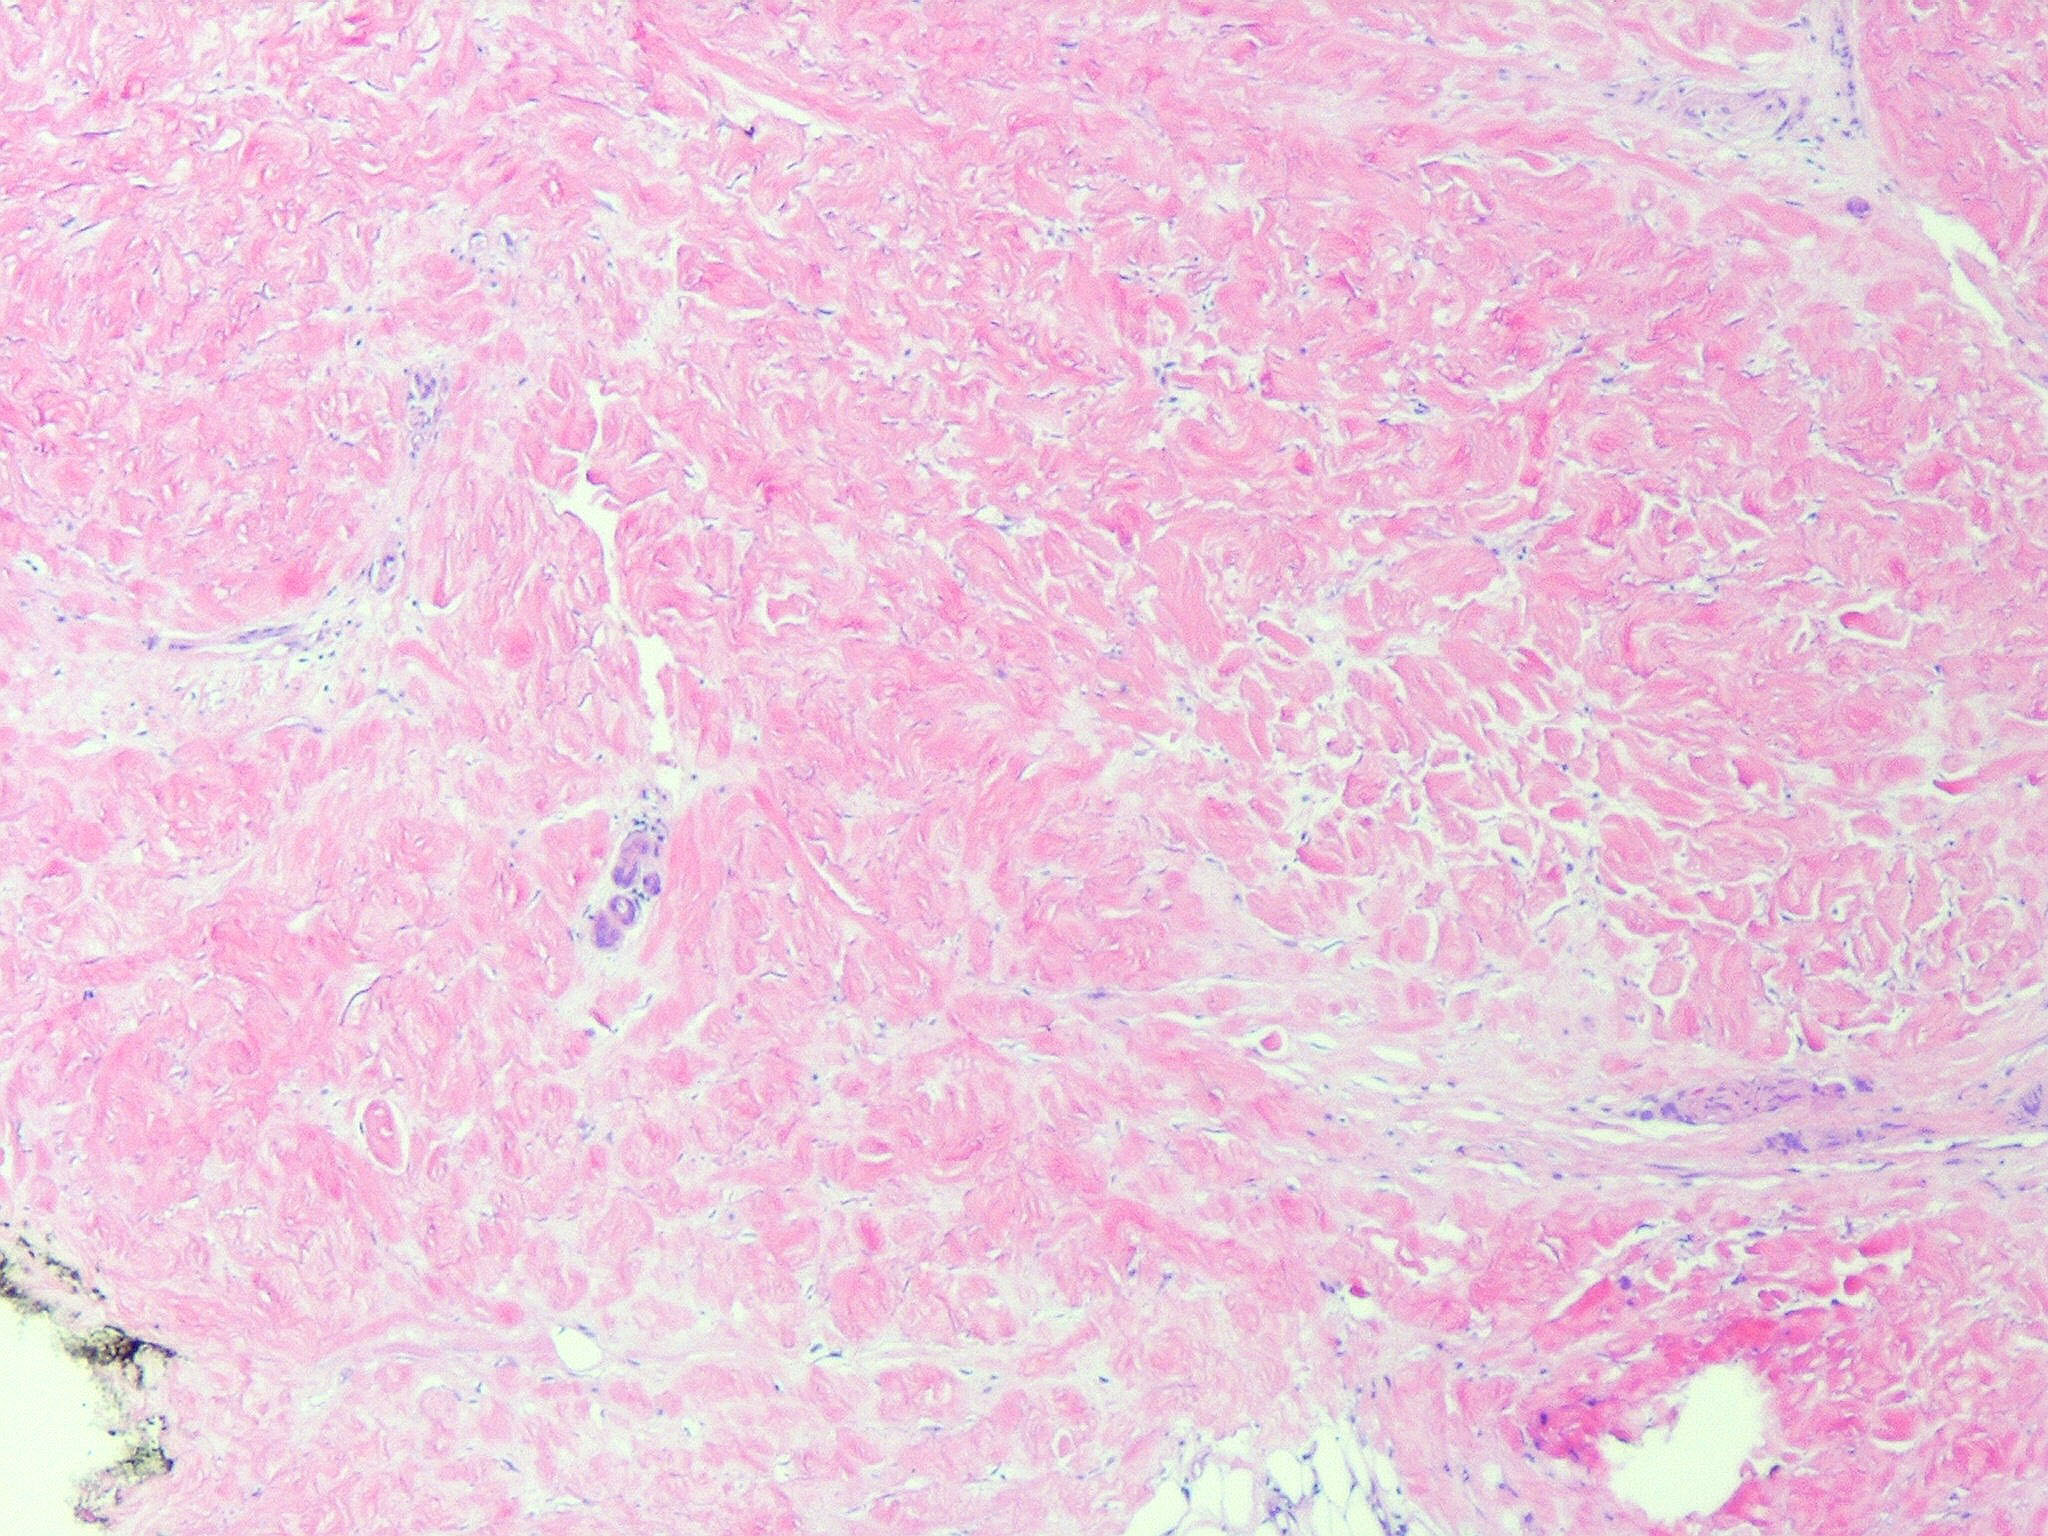

morphea